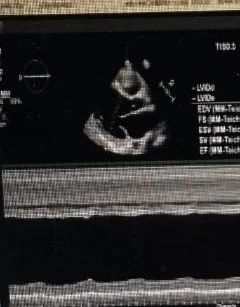

心脏大血管外科曾志华博士为其完善了一系列检查:其中心脏超声显示:全心扩大,以左心为主;二尖瓣重度反流;三尖瓣、主动脉瓣轻中度反流;左右心室收缩功能减低, LVEF26%。属于终末期心衰状态。